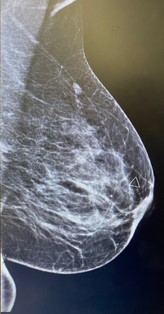

Left breast and axilla ultrasound and Mammogram showed: Left breast palpable lesion with architectural distortion in the upper lateral mid/anterior third at 3:00, It measures 0.9 cm and seen with no significant vascularity. A clip was placed.

Figure 2: Left mammographic views CC of the left breast showing an irregular, spiculated, high-density mass in the upper outer quadrant. The lesion causes architectural distortion without associated calcifications. Findings are consistent with desmoid-type fibromatosis confirmed on histology.

Mammography presents irregular walled and highly dense lesion with no calcifications mimicking sometimes breast carcinoma [6].

Radiologic evaluation of our case revealed soft tissue mass inducing architectural distortion.